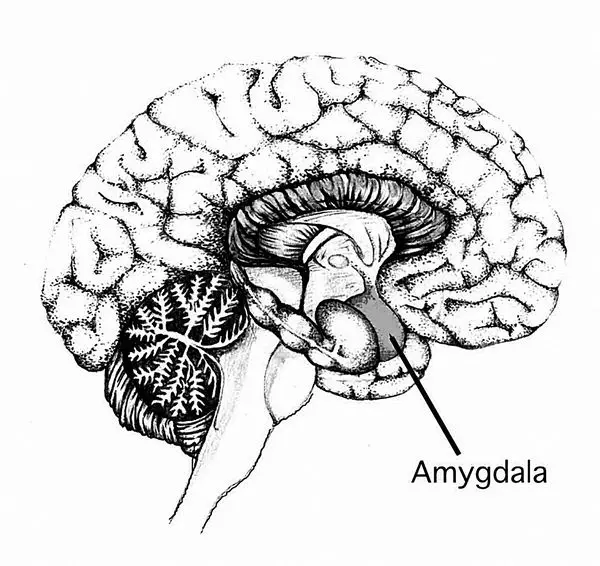

Миндалина – отдел мозга, отвечающий за обработку социально значимой информации

Носители аллеля RS3 334 выделились еще рядом характерных особенностей. Так, их больше среди тех, кто страдает аутизмом. При рассматривании посторонних лиц у носителей этого аллеля сильнее возбуждается миндалина – отдел мозга, отвечающий за обработку социально значимой информации, а также за ощущение страха и недоверчивость.